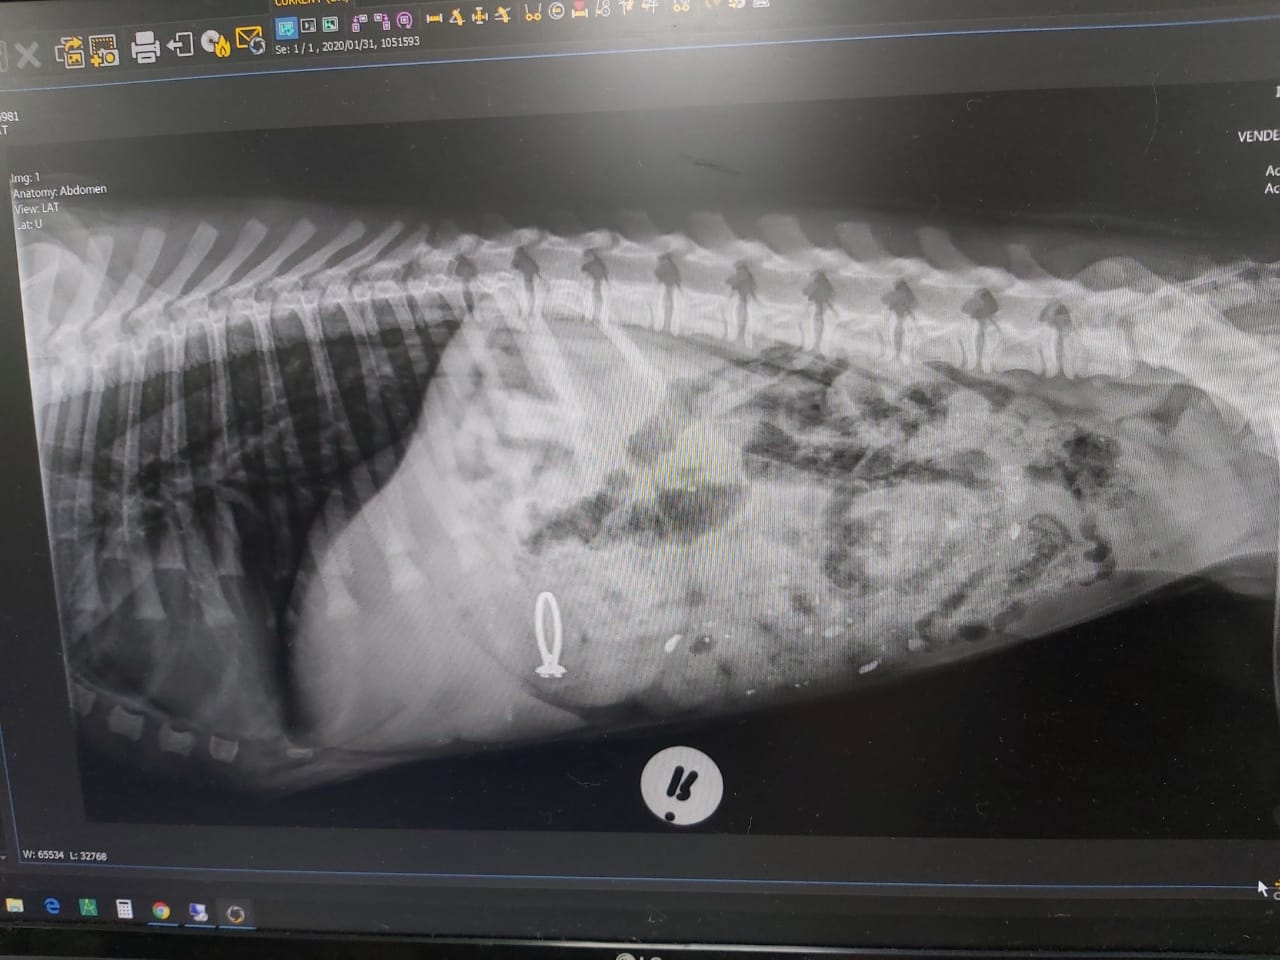

Хозяйка немедленно отвезла собаку в ветеринарную клинику. Пепперу сделали рентген. Выяснилось, что он проглотил кольцо.